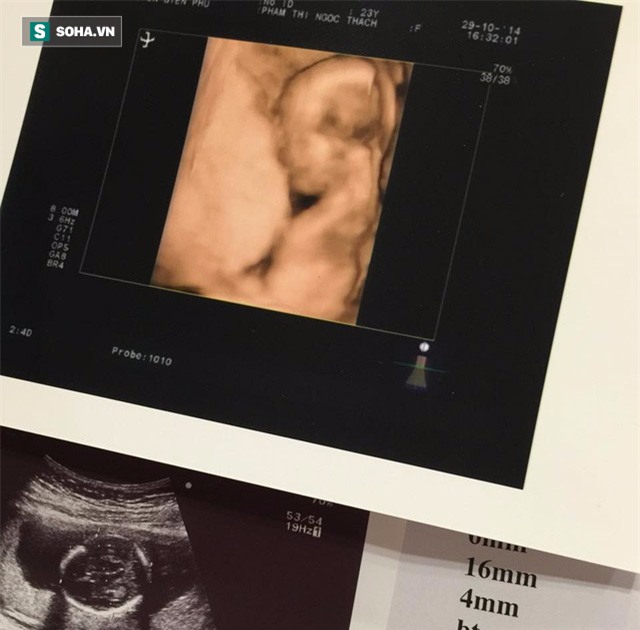

1. Theo dõi sự phát triển của thai dựa vào cân nặng trên siêu âm

Siêu âm là một căn cứ để có thể biết được trẻ có phát triển bình thường hay không

2. Siêu âm và xét nghiệm tầm soát dị tật thai để biết thai có hoàn toàn khỏe mạnh hay không